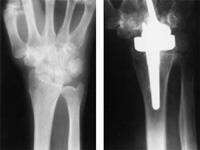

Wrist joint replacement

X-ray of a wrist with severe rheumatoid arthritis throughout the wrist before (left) and after (right) replacement of the wrist joint with an implant.

Reproduced with permission from Carlson JR, Simmons BP: Total Wrist Arthroplasty. J Am Acad Orthop Surg 1998;6:308-315.